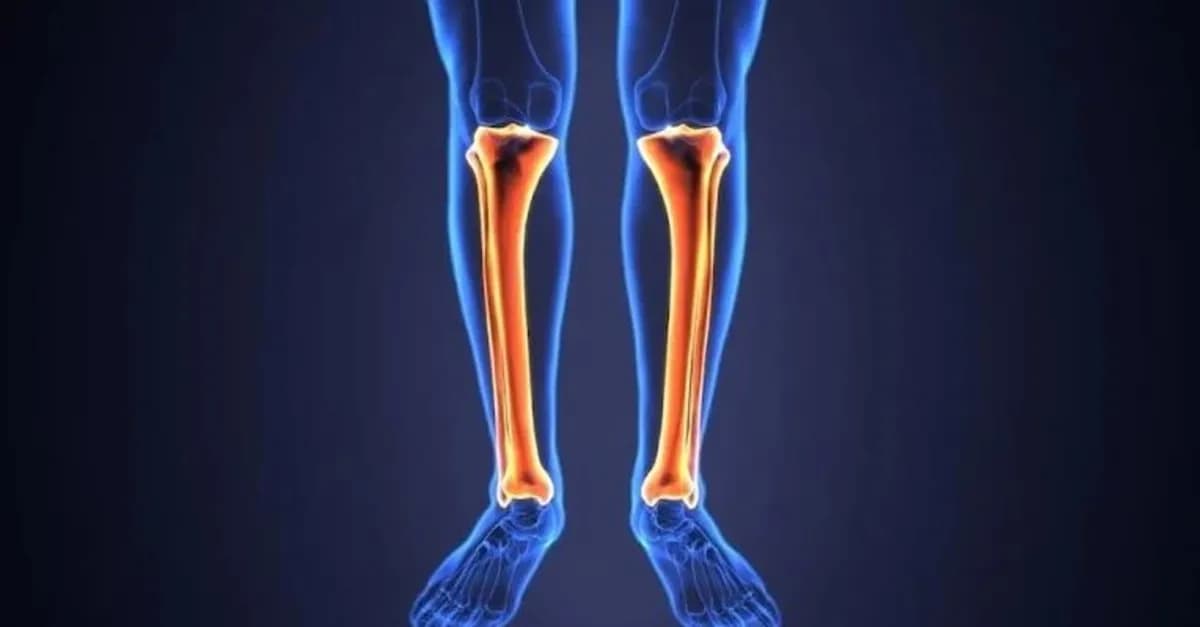

Kaval Kemiği

Kaval Kemiği ya da tibia kemiği, insan vücudunun en önemli destek yapı taşlarından biridir. İnsan vücudunun neredeyse...